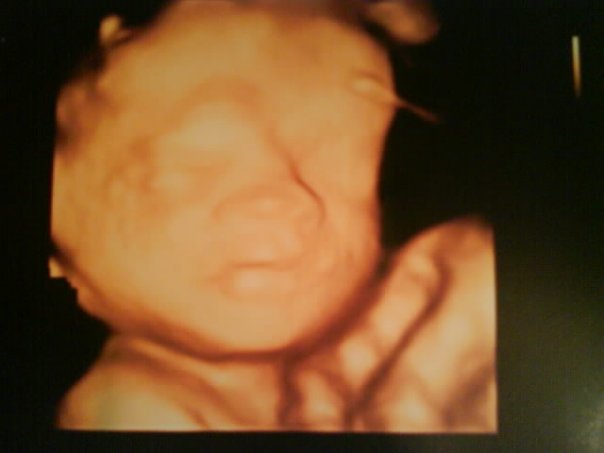

SkumGummi Skrevet 18. mars 2009 Forfatter #311 Skrevet 18. mars 2009 (endret) STOR OPPDATERING!!! - Uke 26 - Jordmorkontroll - 3D Ultralyd - Oppdatert "veien til termin" - Mine "tall gjennom svangerskapet" Uff, beklager... Jeg merker jeg er VELDIG dårlig på å oppdatere! :dåne: Men det kan være fordi jeg synes at responsen på dagboken min har dabbet VELDIG av, og derfor bruker jeg mer tid på bloggen min enn å sitte her å skrive ting "ingen" Men nå får jeg oppdatere til dere få som faktisk følger med! Nå er jeg i uke 26 faktisk - tiden flyr? Litt om henne denne uken "Tulla vår er denne uken 30 cm lang og veier ca 800 gram. Det blir mindre og mindre plass i livmoren. :jentebaby: Øyenvippene dukker opp denne uken, og øynene vil snart kunne åpnes og lukkes. Hjernen vokser fremdeles fort og hun har blitt en velproposjonert liten minibaby. Håret på hodet begynner å bli lengre.Jeg fungerer som en vugge når jeg går omkring og derfor slapper hun ofte av når jeg er aktivitet men kviker til så fort jeg har tenkt til å slappe av! Alle sansene er ferdig utviklet og lille gullet kan se sterke lys igjennom magen!" 3D Ultralyd Mandag var vi på 3D ultralyd på Oslo City Legesenter. Det gikk ikke lenge før hun snudde seg nedover og med hodet innover og da sier det seg selv at det ikke er så lett å få fine bilder. Derfor fikk vi ny (og gratis ) time på torsdag kl halv fire for å se om vi får sett noe mer da. Fikk beskjed om at det var lurt å drikke en flaske cola og spise sjokolade rett før vi kom. Så da skal vi tilbake på torsdag og forhåpentvis se enda mer, få flere bilder og film. Men ja... Vi fikk jo se noe da, før hun snudde seg. Og fikk et bilde med oss hjem. Hun gjespet så det ut som, puttet hånden i munnen også snudde hu seg og da var det slutt på moro'a for mamma og pappa. Vi fikk også en grundig gjennomgang av anatomien til den lille skjønne og alt så veldig veldig bra ut og alt var normalt. Jeg synes så klart hun så helt nydelig ut. :sjenet: Hjerterytmen hennes ble mål til 144, så den lå jo likt som før også veide hun 890 gram og ble estimert til å veie ca 3200-3400 gram når hun blir født. Det synes jeg ikke hørtes så værst ut, men så klart - det kan jo forandre seg Jordmorkontroll Tirsdag var jeg først på kontroll hos jordmor og deretter hos fysioterapaut. Det gikk veldig bra hos jordmor som vanlig og alt sto bra til! Hun synes fastlegen min målte symfysen veldig høyt så nå satt hun symfysemålet mitt litt ned. Hehe - så nå ligger jeg akkurat på gjennomsnittet - på den røde streken. Ellers sa hun at jeg så veldig flott ut og hun sa at jeg kun har lagt på meg det jeg "må" og det var babyen og alt som hørte med der, jeg har ikke lagt på meg noe ellers - noe hun synes var flott. Hun inviterte oss også på fødselsforberedende kurs som hun skulle holde i slutten av april, så det virket veldig interessant og noe vi helt sikkert kommer til å være med på. Vi skal jo på kurs på ullevål men det varer bare 1 time og er litt sånn "fort og gæli". Dette kurset hun hadde var over to kvelder med tre timer hver kveld Mine tall fra jordmorkontrollen: Dato: 17. mars 2009 Uke: 26 (25+3) Vekt: + 4,5 kg (fra før graviditet) Mitt blodtrykk: 110/50 Urin: Ingen merknad Fosterlyd: 140 Symfyse/fondusmål: 23 cm Fikk nye timer til kontroll følgende datoer: 21. april (30+3) 26. mai (35+3) 18. juni (38+5) 2. juli (40+5) (event. overtidskontroll) Fysio Hos fysio fikk jeg først masse informasjon om bekkenløsning før hun gikk igjennom noen "tips til hverdagen" og viste meg litt øvelser osv jeg kan gjøre for å minske belastningen på bekkenet. Jeg sa jeg ikke følte det var nødvendig å sette meg opp på nye timer for behandling imed at jeg føler bekkenet ikke er så værst om dagen! Bilder! Vedlagt følger to bilder; Et fra 3D ultralyd, og siste magebilde. Her er en oppdatert: "veien frem til termin" Kontroller Mitt svangerskap Babyens utviking osv ___________________________ 2009 ___________________________ 02.07: Event. overtidskontroll 29.06: Termin (mens + ul) 18.06: Jordmorkontroll (38+5) 08.06: Svangerskapsperm 29.05: 8 mnd 26.05: Jordmorkontroll (35+3) 26.05: Kurs om barseltiden Ullevål 12.05: Kurs om fødsel + omvisning Ullevål 02.05: Snuppa snur seg (32+0) 28.04: 7 mnd 23.04: Fødselsforberedende kurs jordmor 21.04: Jordmorkontroll (30+3) 16.04: Fødselsforberedende kurs jordmor 04.04: 3. trimester starter 28.03: 9 av 10 overlever (27+0) 27.03: 6 mnd 19.03: Ny 3D ultralyd (19+3) 17.03: Time hos fysio (25+3) 17.03: Jordmorkontroll (25+3) 16.03: 3D Ultralyd (25+2) 03.03: Legetime (bekken) (23+3) 03.03: Jenta hikket (23+3) 28.02: Jenta vår hører (23+0) 24.02: 5 mnd 07.02: Tulla får søvnmønster (20+0) 02.02: Fått råmelk (19+2) 26.01: Ordinær ultralyd 24.01: Kjente spark (18+0) 23.01: 4 mnd 13.01: Legetime (16+2) 12.01: Kjente bevegelse (16) 10.01: Svelger og tisser ___________________________ 2008 ___________________________ 27.12: Kjønnet tydelig (13+6) 23.12: 3 mnd 22.12: Kvalmfri dag (13+1) 20.12: Kvalmen avtar for de fleste 15.12: 2. trimester starter 17.12: Privat ultralyd (12+3) 13.12: Risiko for å miste avtar 08.12: Kjente livmoren (11+1) 04.12: Jordmortime (10+4) 01.12.09 - 11.1.09: 100 % sykemeldt pga kvalme 29.11: Organer ferdig (9+6) 29.11: Embryo slutt (9+6) 24.11-01.12: 50% sykemeldt 22.11: 2 mnd 22.11: Beveger seg (8+6) 14.11: Større bryster (7+5) 05.11: Oftere tisse (6+3) 30.10: Kvalme/oppkast (5+4) 29.10: Hjertet slår (5+3) 27.10: Første legetime (5+1) 23.10: Stikking i magen (4+4) 22.10: 1 mnd 20.10: Positiv test (4+1) 20.10: Uggen i kroppen (4+1) 18.10: Ømme bryster (3+6) 13.10: Trettere enn før (3+4) 04.10: Jenta vår ble skapt (ca) Min vekt i svangerskapet (Regnet + eller - fra vekt før graviditet) 17.03.09 (25+3): + 4,5 kg 04.03.09 (23+4): + 2,7 kg 26.02.09 (22+5): + 1,7 kg 11.02.09 (20+4): + 0,6 kg 04.02.09 (19+4): - 0,1 kg 26.01.09 (18+1): - 1,1 kg 15.01.09 (16+4): - 2,4 kg 09.01.09 (15+5): - 2,9 kg 01.01.09 (14+4): - 4,2 kg 19.12.08 (12+5): - 6,1 kg Mitt blodtrykk 17.03.09 (25+3) - 110/50 03.03.09 (23+3) - 130/78 11.02.09 (20+4) - 120/70 26.10.008 (5+1) - 130/103 Symfyse/fondusmål 17.03.09 (25+3) - 23 cm 03.03.09 (23+3) - 24 cm 11.02.09 (20+4) - 17 cm Jenta vår sin hjertelyd 17.03.09 (25+3) - 140 16.03.09 (25+2) - 144 03.03.09 (23+3) - 144 11.02.09 (20+4) - 140 26.01.09 (18+1) - 149 13.01.09 (16+2) - 148 17.12.08 (12+3) - 168 Endret 18. mars 2009 av SkumGummi